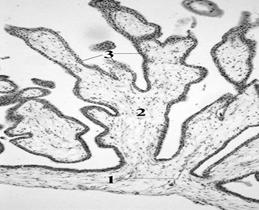

| Рис.122. Строение стенки хориона. 1 – кровеносные сосуды в хориальной пластинке; 2 - ворсинка; 3 - трофобласт. |